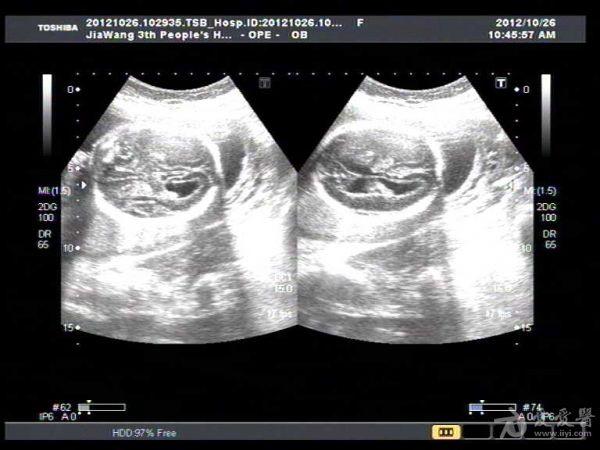

此孕妇22岁,于孕六月来我院产检,可见胎儿侧脑室扩张积液约1.4Cm,遂告知小孩脑

积水,此孕妇接着去我们当地三甲医院检查,也被告知胎儿脑积水,建议引产。